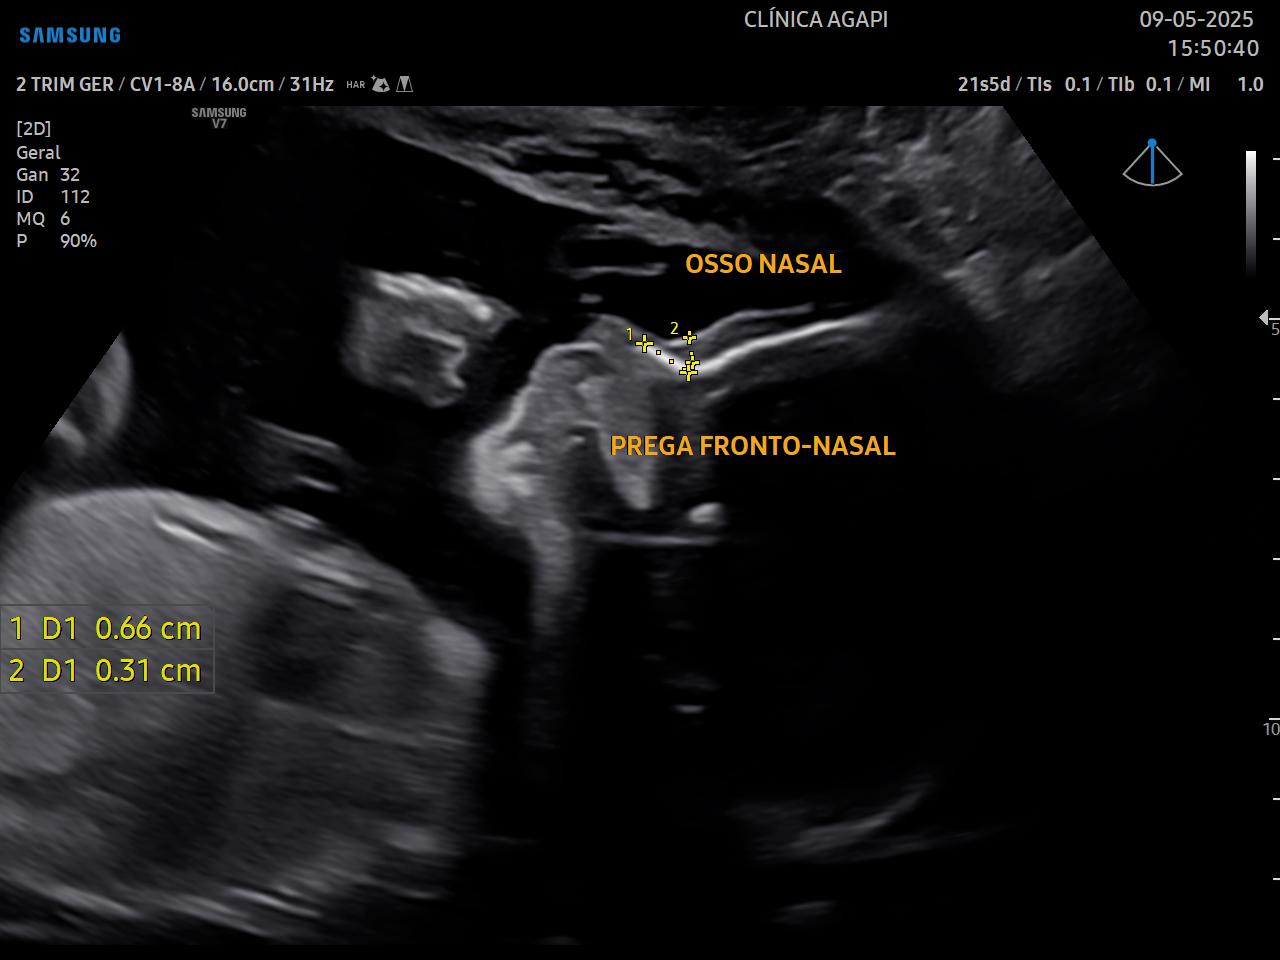

Realizado preferencialmente entre 20 e 24 semanas de gestação, seu objetivo principal é avaliar a anatomia fetal de forma detalhada e detectar possíveis malformações.

Além da análise fetal, também avaliamos a placenta, líquido amniótico e peso. Recomenda-se neste período a medida do colo uterino pela via transvaginal para avaliação de risco de prematuridade.

Aqui, o exame é sempre completo, incluindo o transvaginal e o doppler das artérias uterinas.